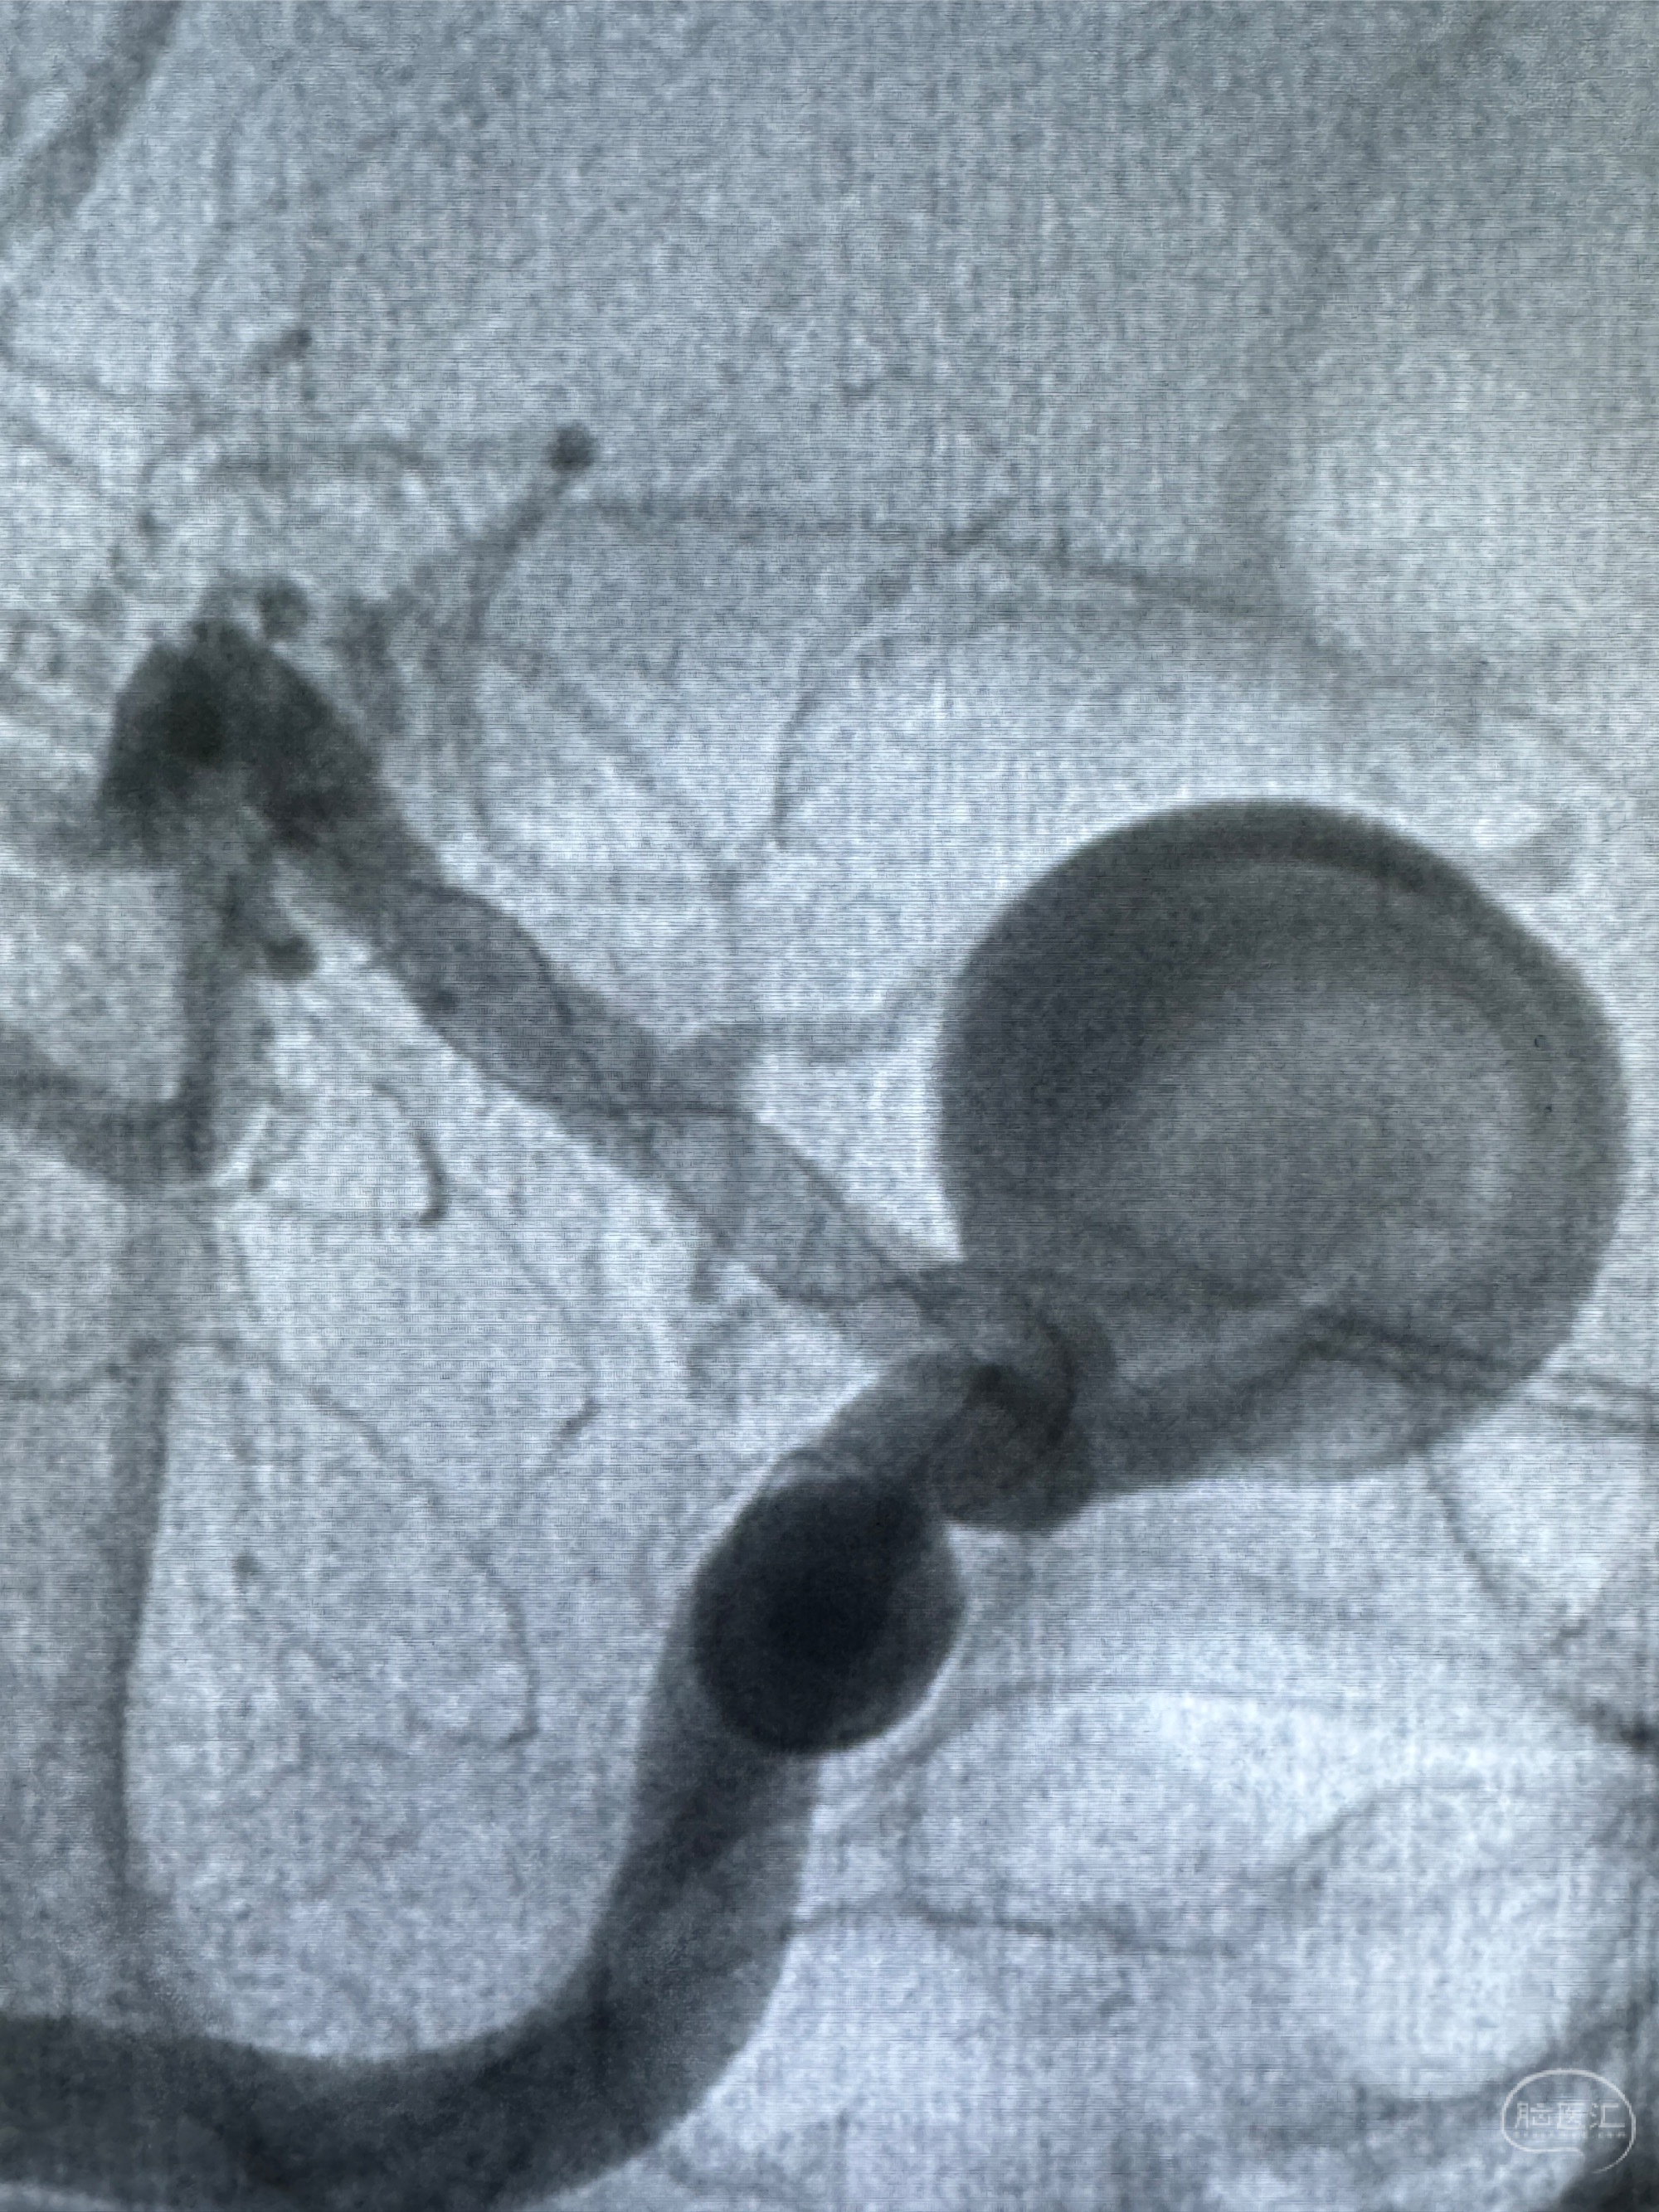

2023-12-27术后第十天复查DSA

支架贴壁佳,但可见射流,咋办?

2024-01-08全麻下再行植入密网支架一枚

Tubridge 4.5-35mm

支架植入顺利,贴壁佳,支架内血流通畅,动脉瘤内血液滞留明显